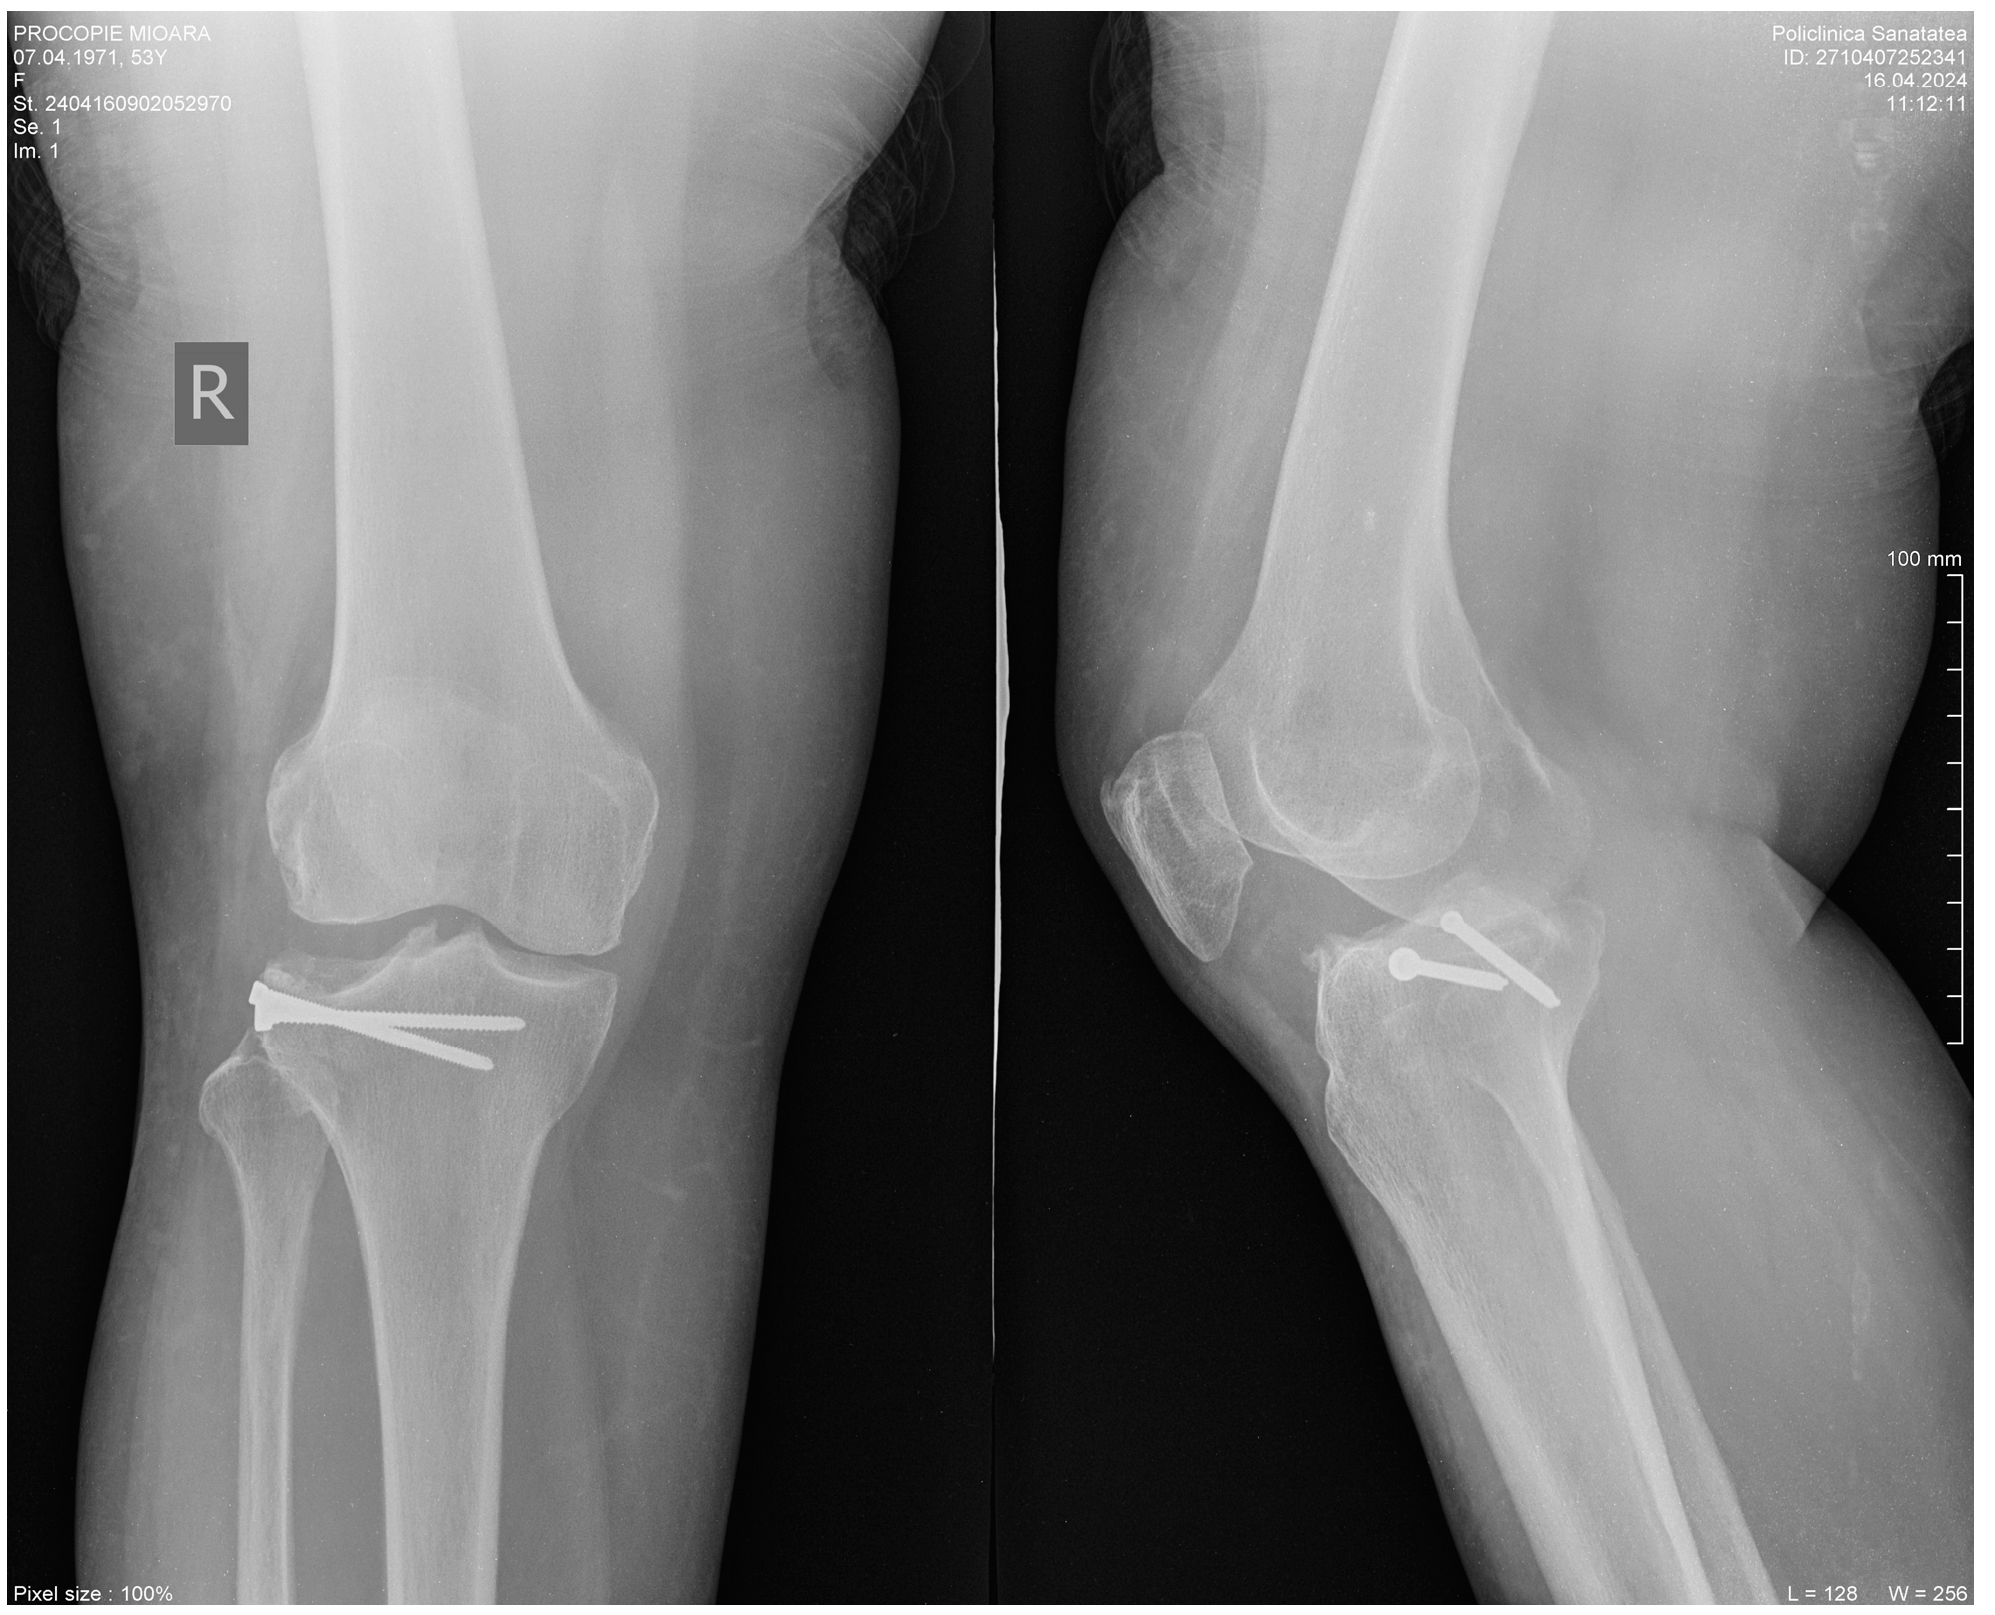

2. Clinical Case Presentation